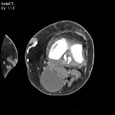

Синовиальная киста подколенной ямки. Синовиальная киста подколенной ямки OpenWindow.document.write("Medicus Amicus - Медицинские изображения")

Пациент R., 59 лет

Синовиальная киста подколенной ямки.

ЦКБ5 Южной железной дороги, отделение лучевой диагностики.

Протокол.

Контрастированы поверхностные и глубокие вены левого коленного сустава. Костно-деструктивные изменения не определяются. Дегенеративно-дистрофические изменения в проксимальном бежберцовом сочленении. В области подколенной ямки, прилежа медиально и кзади к подколенной мышце, полостное образование размерами 42х36х56 мм, содержащее жидкость (16-20 HU) с четкими ровными контурами, без признаков сдавления глубоких вен подколенной ямки.